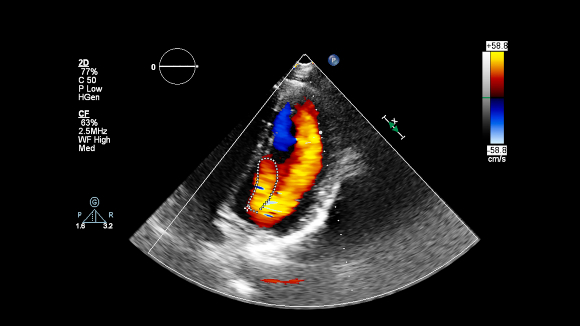

שימוש רפואי רב, לא רק בגינקולוגיה. סריקת אולטרסאונד של הלב המראה בצבע את כיווני הזרימה של הדם בעזרת אפקט דופלר | צילום: faustasyan, Shutterstock

ואכן, עוד בחייו של דונלד בדיקות האולטרסאונד הרפואיות התרחבו הרבה מעבר לתחום הגינקולוגיה והמיילדות, והן משמשות היום גם לאבחונים של מחלות ומצבים רפואיים רבים, בהם גידולים סרטניים מסוימים, כפי שחזו ויילד ועמיתיו. בנוסף, גם סקירות ההיריון באולטרסאונד השתכללו מאוד, כמו שהוא עצמו צפה, וכיום המכשירים מספקים תמונות צבע תלת-ממדיות, שנוסף על ההנאה הוויזואלית להורים שבדרך, מאפשרות גם אבחונים מפורטים להדהים של מצב העובר. בכל יום נעשות ברחבי העולם מיליוני סריקות על-קוליות, וגאוותו הגדולה של דונלד הייתה שפיתח כלי המשפר את האבחון הרפואי.